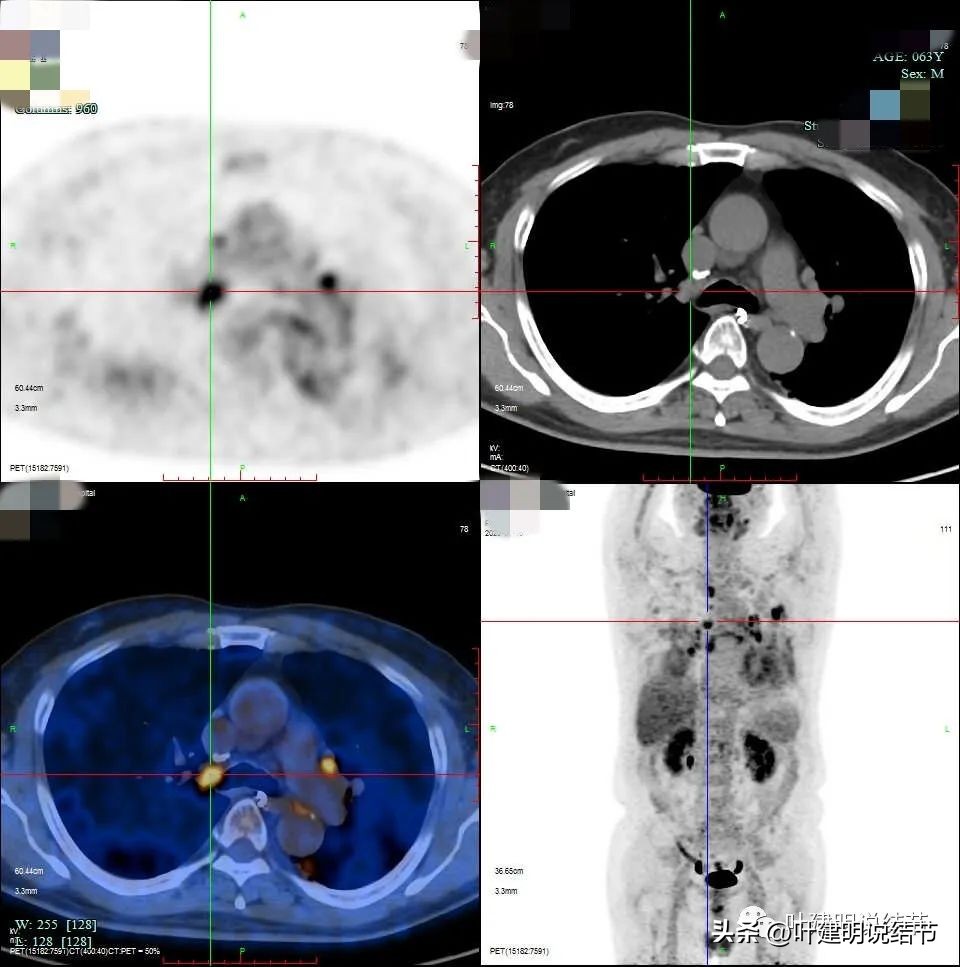

有钙化是不是考虑良性的呢?一般来说病灶伴钙化容易是良性,但这个病例恶性的影像太多太明显,所以再来看PET影像:

病灶处

右侧给隔淋巴结

右侧肺门淋巴结

左侧淋巴结